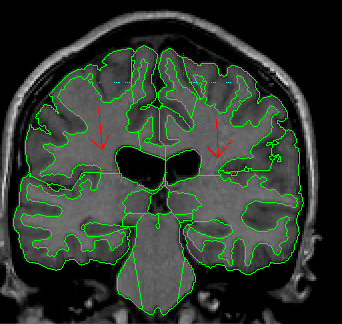

Step Three: When the Temporal Lobe connects with the Frontal Lobe draw a straight, horizontal line (in the coronal view) from the inferior tip of the insula to the medial frontotemporal junction (Fig 13). Extract the cortex that is between the inferior tip of the insula and this line (Fig 14). Do this for both hemispheres and label as Frontal Lobe. While there is no Central Sulcus present, label all cortex superior to the insula as Frontal Lobe.

Figure 13

Figure 14

Step Four: When the Central Sulci lines drawn in the axial view appear in the coronal view (as “dots”) (Fig 15), connect the exterior at this sulcus with the white matter medial to it with a straight line (Fig 16). Extract the cortex superior to this and label it as Frontal Lobe (Fig 17).

Figure 15

Figure 16

Figure 17